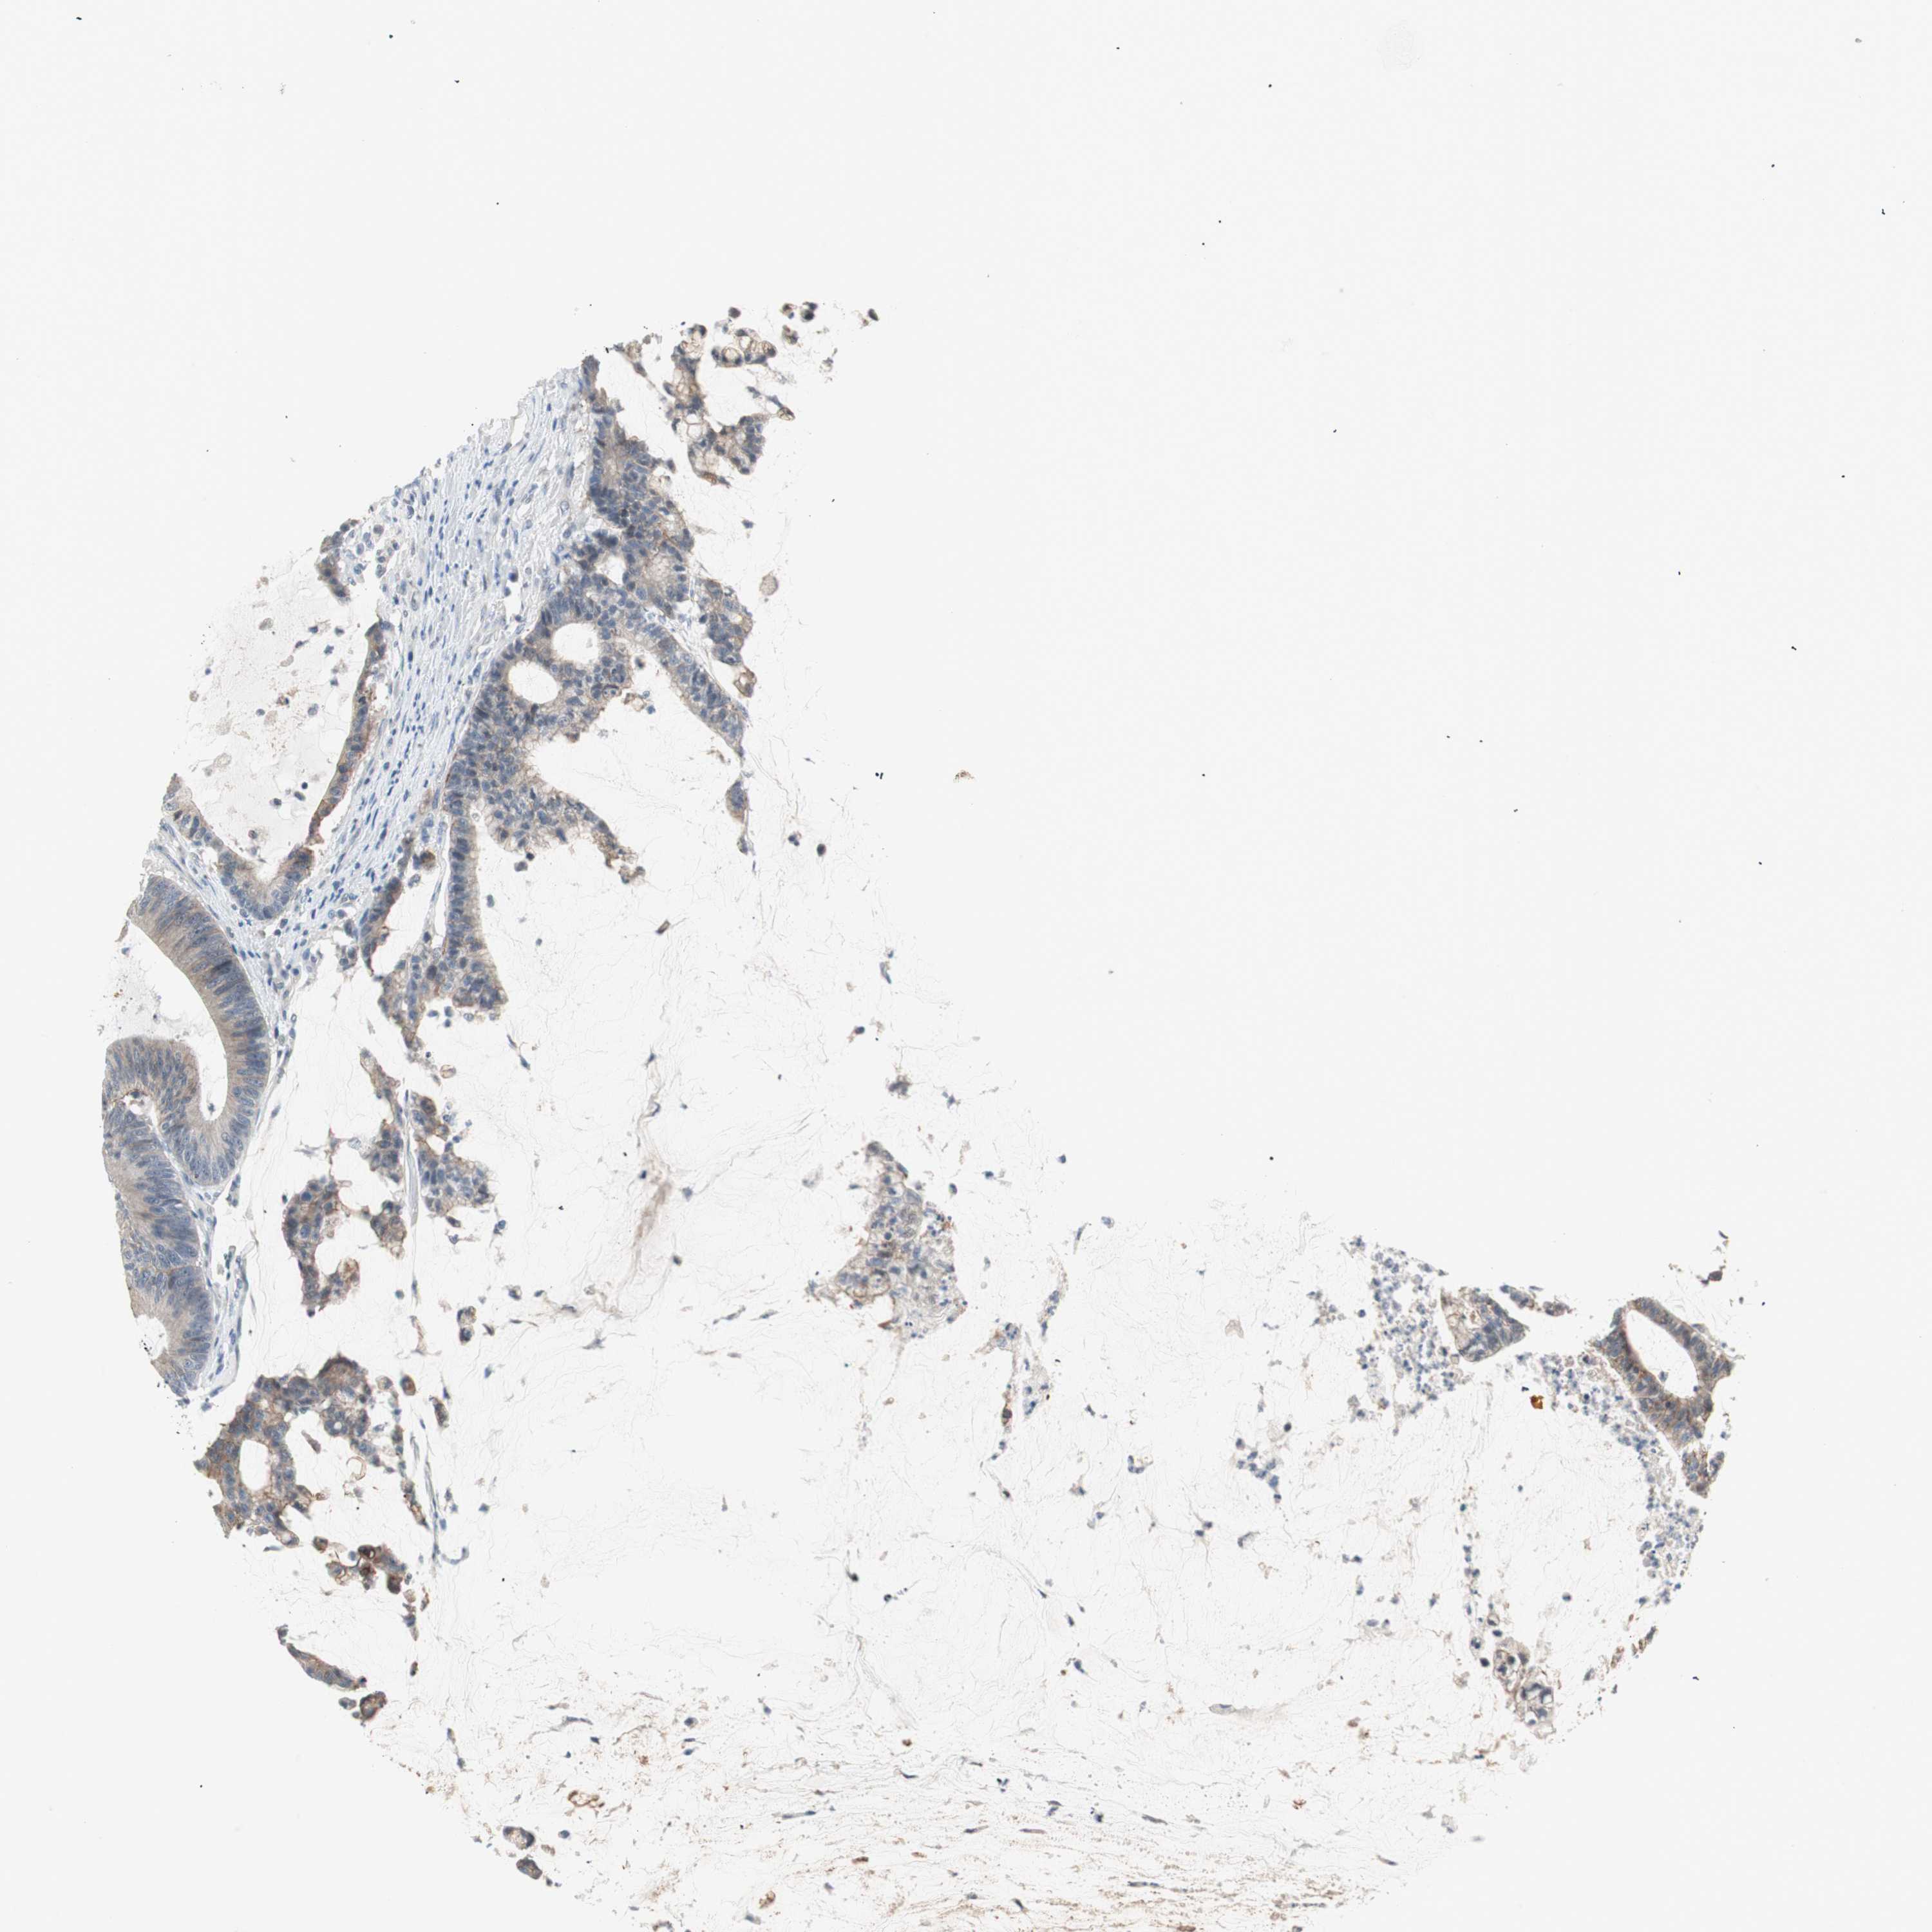

CANCER COLORECTAL CANCER Show tissue menu

Colorectal cancer

Human cancer

Colon adenocarcinoma